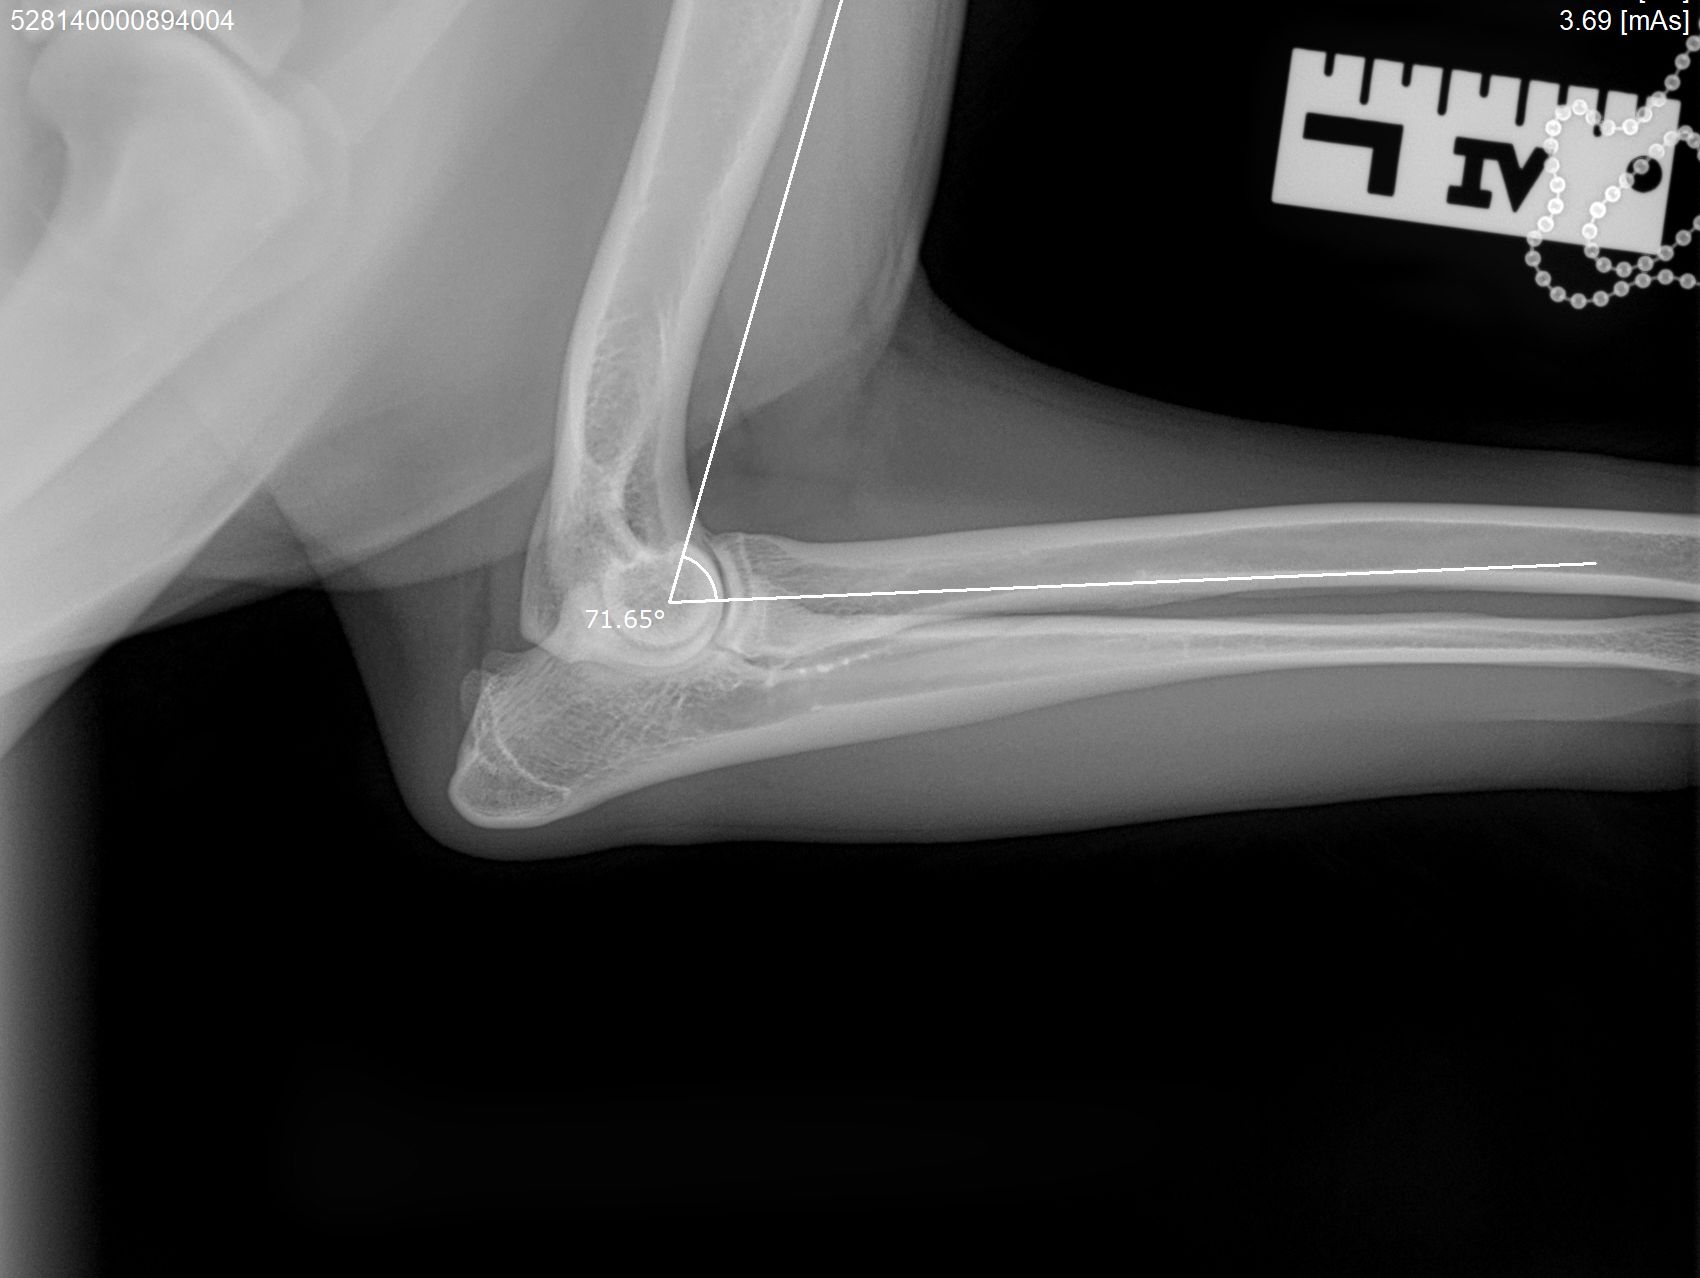

Hieronder foto's van Guus genomen met onze nieuwe DRgem rontgen. Beoordeeld met de hoogste score door de Raad van Beheer op Kynologisch gebied

Elleboogdysplasie (ED) onderzoek

Elleboogdysplasie is een ontwikkelingsstoornis van de ellebooggewrichten, met name het kraakbeen is aangetast. Deze aandoening kan erfelijk zijn, maar omgevingsfactoren spelen soms ook een rol. Er zijn honden die op jonge leeftijd al problemen ondervinden door ED, soms komt het pas op latere leeftijd tot uiting. Om te kunnen zien of uw hond ED heeft zijn röntgenfoto’s van de ellebogen nodig.

Voor een aantal rassen is een diagnose-onderzoek verplicht. Bij dit onderzoek dienen er per elleboog vier foto’s in vier verschillende richtingen gemaakt te worden (dus in totaal 8 foto’s). Deze rassen zijn: Labrador Retriever, Golden Retriever, Chesapeake Bay Retriever, Rottweiler, Berner Sennenhond, Duitse Herdershond, Bordeaux Dog.

Voor alle andere rassen volstaat een onderzoek met twee foto’s per elleboog. Meestal passen wij een lichte sedatie toe bij het maken van de officiële ED-foto’s. Dit is nodig om een kwalitatief goede foto te maken, welke aan de hoge eisen van de beoordelingscommissie moet voldoen. Uw hond moet op zijn of haar zijde en borst liggen, waarbij de elleboog in verschillende houdingen wordt gelegd.